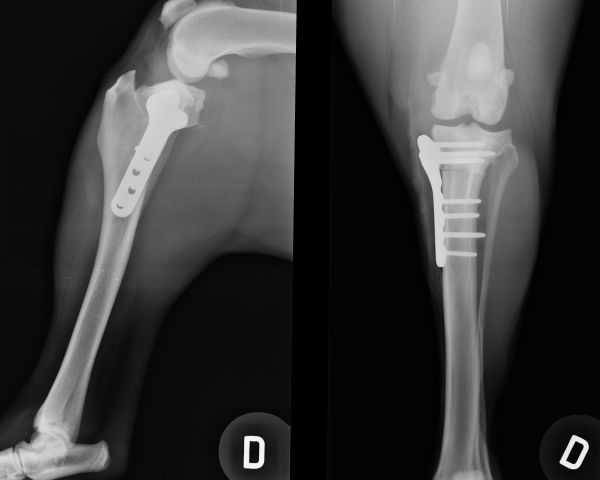

Fraturas, Ruptura de ligamento, dor de coluna, dificuldade de locomoção, claudicação (mancar) implante de proteses, tratamento conservativo, etc

Profissionais especializados em emcirurgias ortopedica (fraturas, ruptura de ligamento, luxações) e de tecidos moles (castração, trato digestivo, urinário, etc)